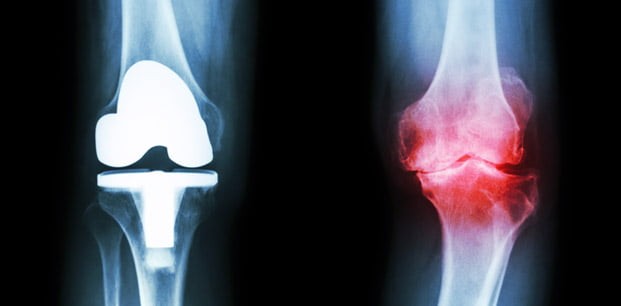

Eklemlerimiz özellikle günlük bazda inanılmaz derecede tekrarlayan yük alırlar bu nedenle yaşlandıkça eklemlerimizin de yıpranması pek de şaşılacak bir şey değildir. Bu yıpranmanın sonucu genellikle artrit olarak bilinir. Aslında artritin 2 türü vardır; romatoid artrit ve osteoartrit. İkincisi daha yaygın olarak görülürken, birincisi daha gizemlidir.

Osteoartrit, eklemlerdeki yük taşınmasını sağlayan kıkırdak yapının zamanla bozularak kemik yüzeylerinin ağ-rılı bir şekilde birbiri ile temas etmesi şeklinde görülür. Bu, genellikle yaşlanmanın bir sonucudur. Fakat buna ek olarak aşırı miktarda yük ya da eklemlerdeki bir ha-sar sebebiyle de olabilir. Romatoid artrit ise biraz daha az anlaşılırdır. Bu, kronik otoimmun sistem bozukluğunun bir sonucudur. Özellikle sinovyali yani vücuttaki eklemleri koruyan yumuşak dokuyu hedef alır. Sonuç olarak, hastalarda alevlenme gibi bir çok ağ-rılı semptomun yanı sıra bazen de kemik erimesi görülebilir. Artritin iki türünün de tam olarak bir çaresi olmamasına karşın, semptomları evde azaltmak epey kolay olabilir.